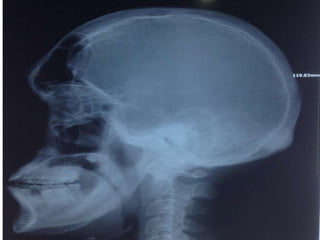

• Thickened skull vault, specially inner table with

encroachment of diploic space.

• Paranasal sinuses and mastoid air cells are enlarged,

Frontal bossing.

• Pituitary fossa : Ballooning of the sella with

undercutting of ant. clinoid process,

backward growth of dorsum , downward

enlargement of floor of sella into the

sphenoid bone

• Prognathism

Acromegaly: frontal sinuses markedly enlarged & there is frontal

bossing.